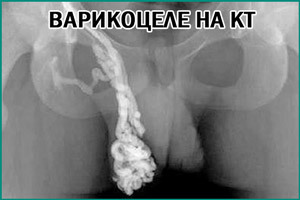

Изредка назначается КТ, МРТ и флебография. В случае крайней необходимости делается биопсия яичка.

Уточняется скорость свертываемости крови. Нередко требуется проведение МРТ и КТ. Эти исследования помогают определить наличие тромбов и патологий, способных спровоцировать появление вторичного варикоцеле.